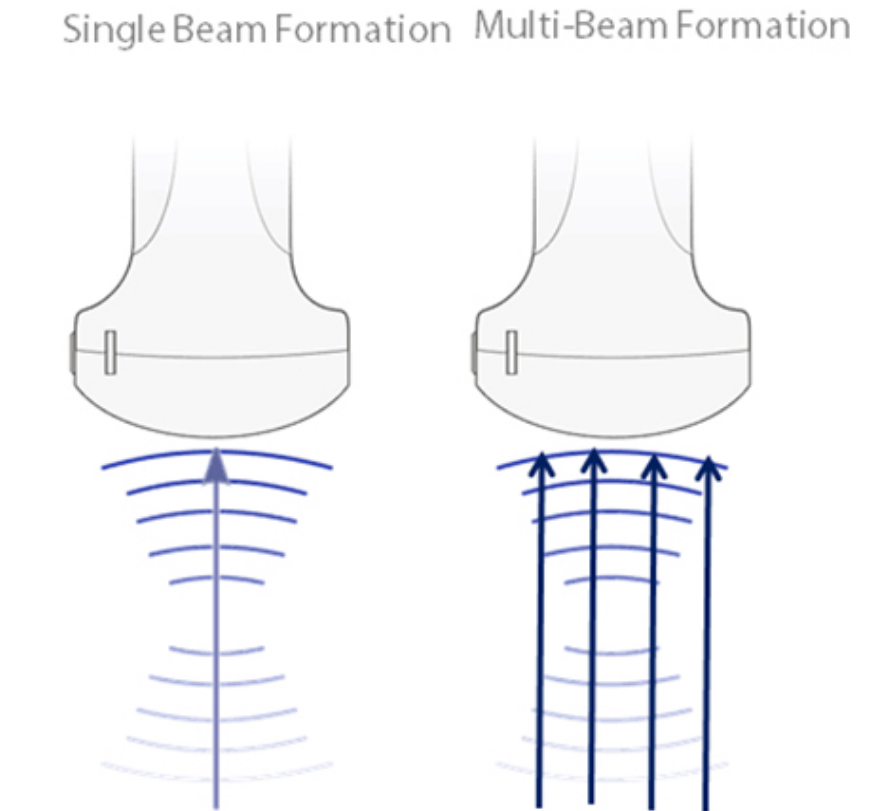

?oklu I??n Olu?turma

Sonucunda m├╝kemmel zamanlama ??z├╝n├╝rl├╝?├╝ ve daha y├╝ksek resim karesi h?z? elde edilen, tek bir aktar?lm?? ???n i?in maksimum 4 defa i?lem s├╝resi.